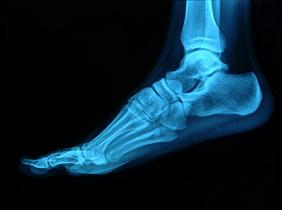

En los resultados del sistema de análisis cinemático se aprecia cómo el pie derecho tiene un tiempo de contacto más corto en todos los pasos debido a la marcha antiálgica (para evitar el dolor). En la baropodometría no se observa el apoyo del talón porque el paciente intenta proteger la zona de impactos y carga.